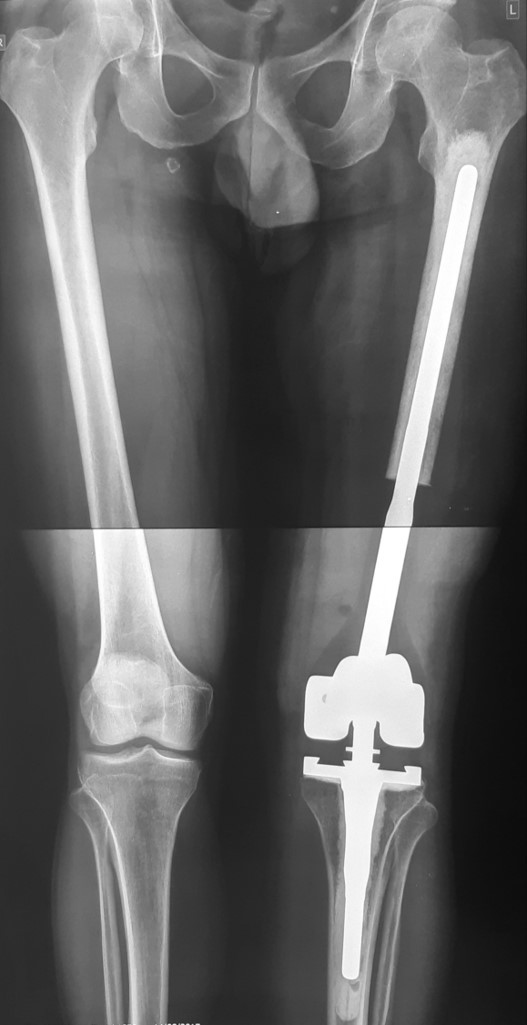

3․Մետաստազ ազդրոսկր + կոնք-ազդրային հոդ

68-ամյա պացիենտի մոտ ախտորոշվել էր թոքի քաղցկեղ։ Անցնելով համապատասխան հետազոտություններ՝ պացիենտի ոսկրային հատվածում հայտնաբերվել էին սոլիտար (եզակի) մետաստազներ: Բուժման նպատակով ՝ վերջինս ստացել է քիմոթերապիայի կուրսեր։

Հաշվի առնելով օրգանիզմի դրական պատասխանը քիմիոթերապիայի և ուռուցքի զգայունությունը դեղորայքի նկատմամբ։ Իրականացվել է ռադիկալ վիրահատություն։ Հեռացվել է ազդոսկրի վերին երրորդականը, առաջացած դեֆեկտը շտկվել է մոդուլային էնդոպրոթեզով՝ վերջույթի ֆունկցիայի կայուն վերականգնմամբ։ 68-ամյա բուժառուն ստացել է հետվիրահատական դեղորդայքային բուժում։ Վերջինս իրեն լավ է զգում։

Վիրահատությունից առաջ

Վիրահատությունից հետո